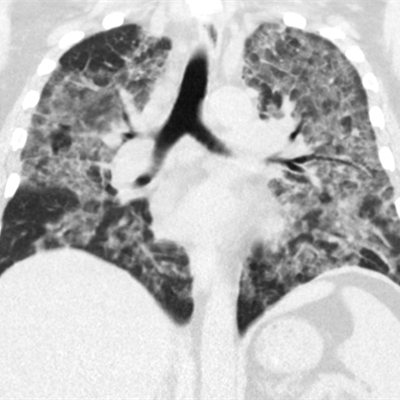

- Giant cell interstitial pneumonia: Hard metal contamination of vaping aerosols is well documented, the authors noted. They encountered one case of this rare pneumonia, which was due to trace amounts of cobalt in the patient's vape mechanism.

Giant cell interstitial pneumonia attributed to vaping in a 49-year-old woman who presented with one to two years of worsening dyspnea. Axial CT images show relatively symmetric ground-glass opacity and perilobular opacities involving all lobes. Subsequent surgical lung biopsy results were consistent with giant cell interstitial pneumonia. When asked about exposure, the patient said she had begun vaping a tetrahydrocannabinol (THC) mixture around the time her symptoms started. She had no other occupational exposures to heavy metals, and her vape pen was found to have traces of cobalt on subsequent analysis. Images courtesy of the American Roentgen Ray Society.Radiologists are an important part of the clinical team when it comes to patients presenting with lung injury, the researchers concluded.